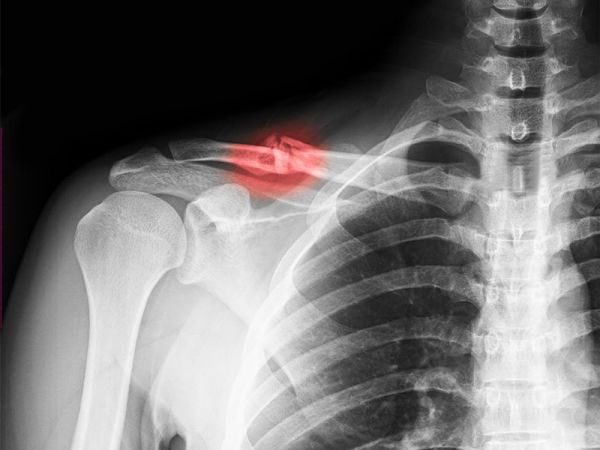

Fratura da Clavícula

As fraturas da clavícula são as fraturas mais comuns do ombro, e correspondem a cerca de 2 a 3% de todas as fraturas. A maior parte das fraturas da clavícula acontece no momento em que ocorre uma queda com trauma no ombro. Acomete principalmente homens jovens com idade abaixo de 20 anos. A maioria (80-85%) das fraturas da clavícula ocorrem no terço médio.

O diagnóstico é feito pela história de queda, o exame físico com dor, inchaço, crepitação na região da clavícula.

O exame inicial que deve ser realizado é uma radiografia. A tomografia computadorizada normalmente não é necessária, sendo realizada em casos complexos ou fraturas da região medial.